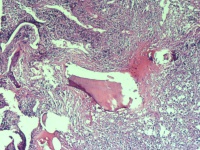

请教老师 骨肉瘤吗?

性别

男

年龄

74岁

腰骶部疼痛不适2月余 CT示骶髂处溶骨性改变伴周围软组织肿胀

标本名称

骶髂处骨组织活检

大体所见

1*1*0.5cm灰红碎组织